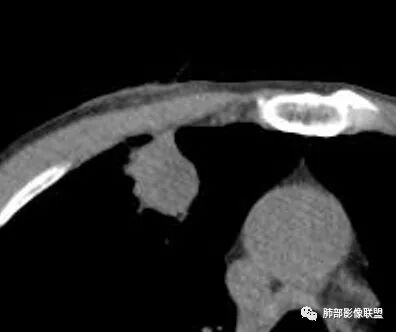

南边:宽基底与胸膜相连桃尖征、U型凹陷、刀切征密度均匀,按理这一部分就是典型的炎性病变的特点

南边:周围晕、细微毛刺都属于炎性特点这一部分单独拿出来类圆形,边缘光滑,按理恶性特征不明显;但是加在一起,转移瘤就不排除总体倾向于炎性,转移瘤不除外

这里毛刺还是粗

转移瘤不能排除

南边:就目前的征象符合炎性,我认为炎性病变一定有但是有部分边缘膨隆,恶性不能排除,等炎性吸收后看看,或穿刺血管纠集南边:

南边:我们担心的,它是在一个转移的基础上,还有合并有炎症,担心这个隐藏在其中,因为它这个边缘,是不是很清楚光滑哈,但是我们都记得转移瘤,他很多都是边界清楚光滑的,对不对。就觉得,中间这个结节跟周围的病灶好像形态、密度各方面都不一致的。我就担心它是一个转移瘤,合并感染,周围炎性病变,中间是一个转移瘤结节这样的就麻烦了。所以常规我会建议他抗炎治疗后复查。看看那个残留的病灶怎么样,本质是如何,要么穿刺,这个病变我只能说炎性它一定有。南边:里面那个病灶就是那个类圆形的病灶,跟外面那个肯定是不一致的,就那个类圆形病灶,到底是一个转移瘤,还是单纯炎性病变的部分。目前这个片只能等复查,毕竟边缘是膨隆的,而且我们刚才也说了,转移瘤的特点,如果血道转移,他就是边界清晰光滑的。所以成这样,有这么巧的话你就没办法。南边:关于血管纠集,它就这样的,炎性病变也可以这样表现,牵拉过来,原理不同,但是影像表现已经表现很类似,我们往往关注支气管。支气管进入这个病灶的表面的时候是否堵塞,或者血管,进入这个病灶里面,是否走行是否自然;这些这些可能价值大一些,但是他是不是一个恶性征象,是;但是它的比例就是在炎性病变也不低。原发呢,不敢说没有,但是一般来说几率偏低吧。